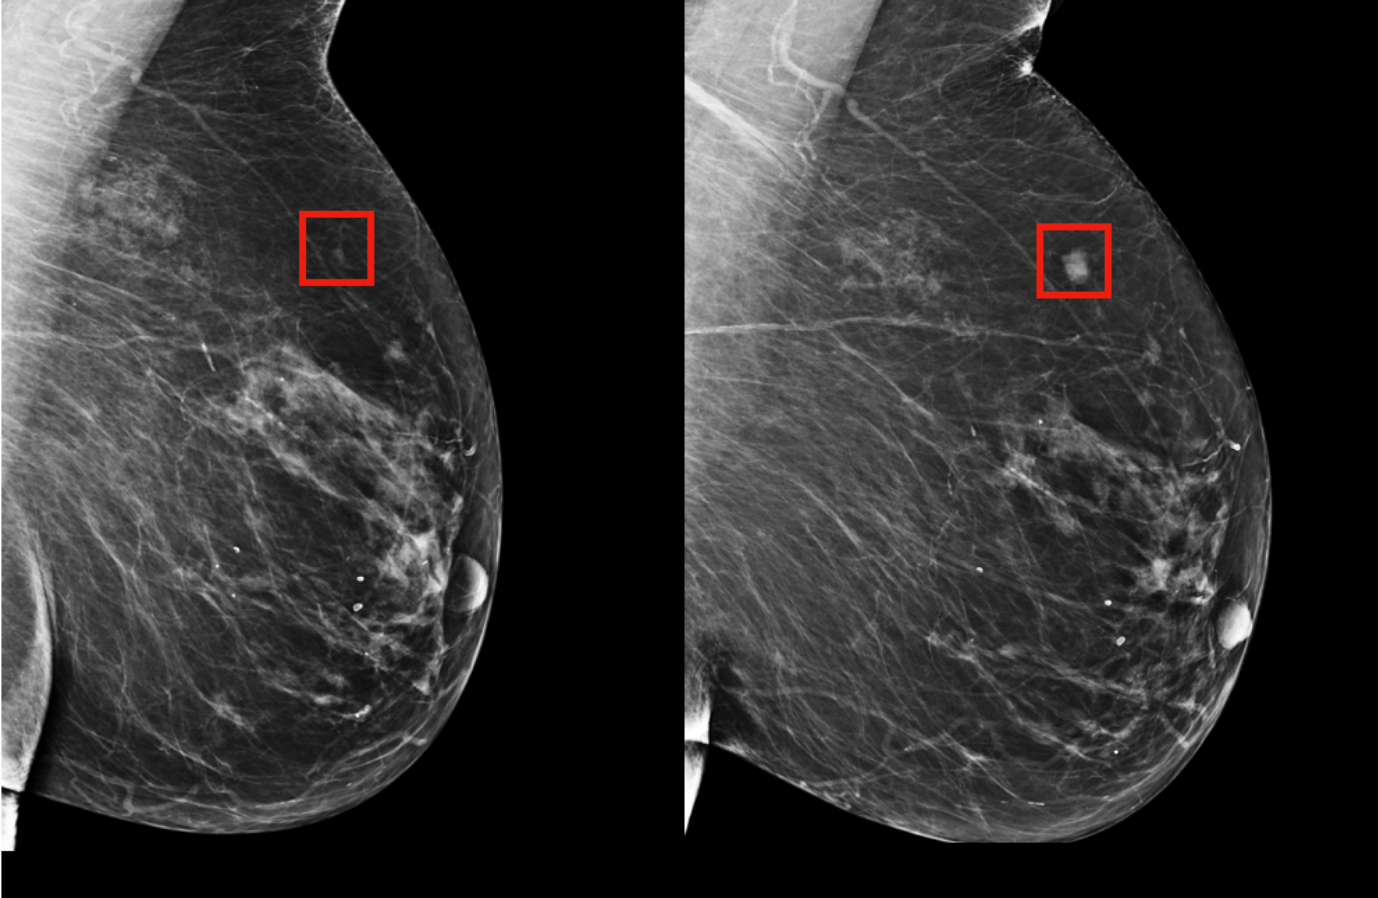

• Breast cancer: 94% detection in dense tissue scans (vs. 79% human)